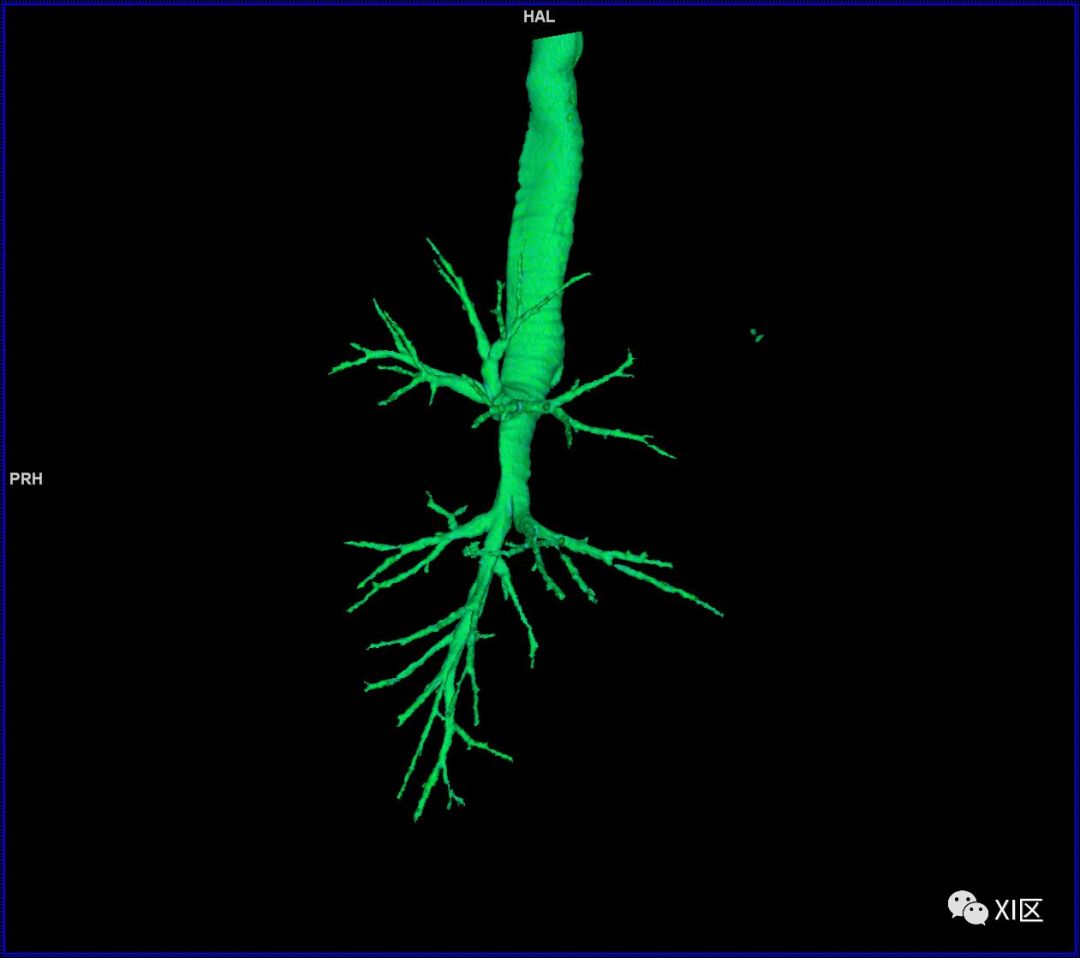

气管支气管树与两肺融合显示

气管树的解剖

人的支气管(第1级)至肺泡约有24级分支。支气管经肺门入肺,分为叶支气管(第2级),右肺3支,左肺2支。叶支气管分为段支气管(第3~4级),左肺8支、右肺10支。段支气管就是肺的分段的依据。段支气管反复分支为小支气管(第5~10级),继而再分支为细支气管(第11~13级),细支气管又分支为终末细支气管(第14~16级)。从叶支气管至终末细支气管为肺内的导气部。终末细支气管以下的分支为肺的呼吸部,包括呼吸细支气管(第17~19级)、肺泡管(第20~22级)、肺泡囊(第23级)和肺泡(第24级)。

气管支气管形如树状,因此也称气管支气管树。

气管树与左右肺的关系

气管树与胸部其他结构的关系